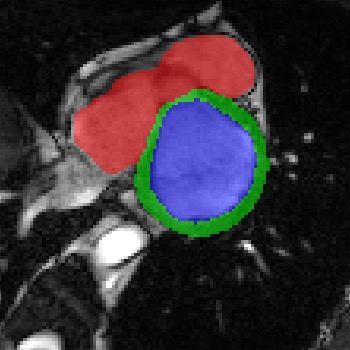

Transformers, the default model of choices in natural language processing, have drawn scant attention from the medical imaging community. Given the ability to exploit long-term dependencies, transformers are promising to help atypical convolutional neural networks (convnets) to overcome its inherent shortcomings of spatial inductive bias. However, most of recently proposed transformer-based segmentation approaches simply treated transformers as assisted modules to help encode global context into convolutional representations without investigating how to optimally combine self-attention (i.e., the core of transformers) with convolution. To address this issue, in this paper, we introduce nnFormer (i.e., Not-aNother transFormer), a powerful segmentation model with an interleaved architecture based on empirical combination of self-attention and convolution. In practice, nnFormer learns volumetric representations from 3D local volumes. Compared to the naive voxel-level self-attention implementation, such volume-based operations help to reduce the computational complexity by approximate 98% and 99.5% on Synapse and ACDC datasets, respectively. In comparison to prior-art network configurations, nnFormer achieves tremendous improvements over previous transformer-based methods on two commonly used datasets Synapse and ACDC. For instance, nnFormer outperforms Swin-UNet by over 7 percents on Synapse. Even when compared to nnUNet, currently the best performing fully-convolutional medical segmentation network, nnFormer still provides slightly better performance on Synapse and ACDC.